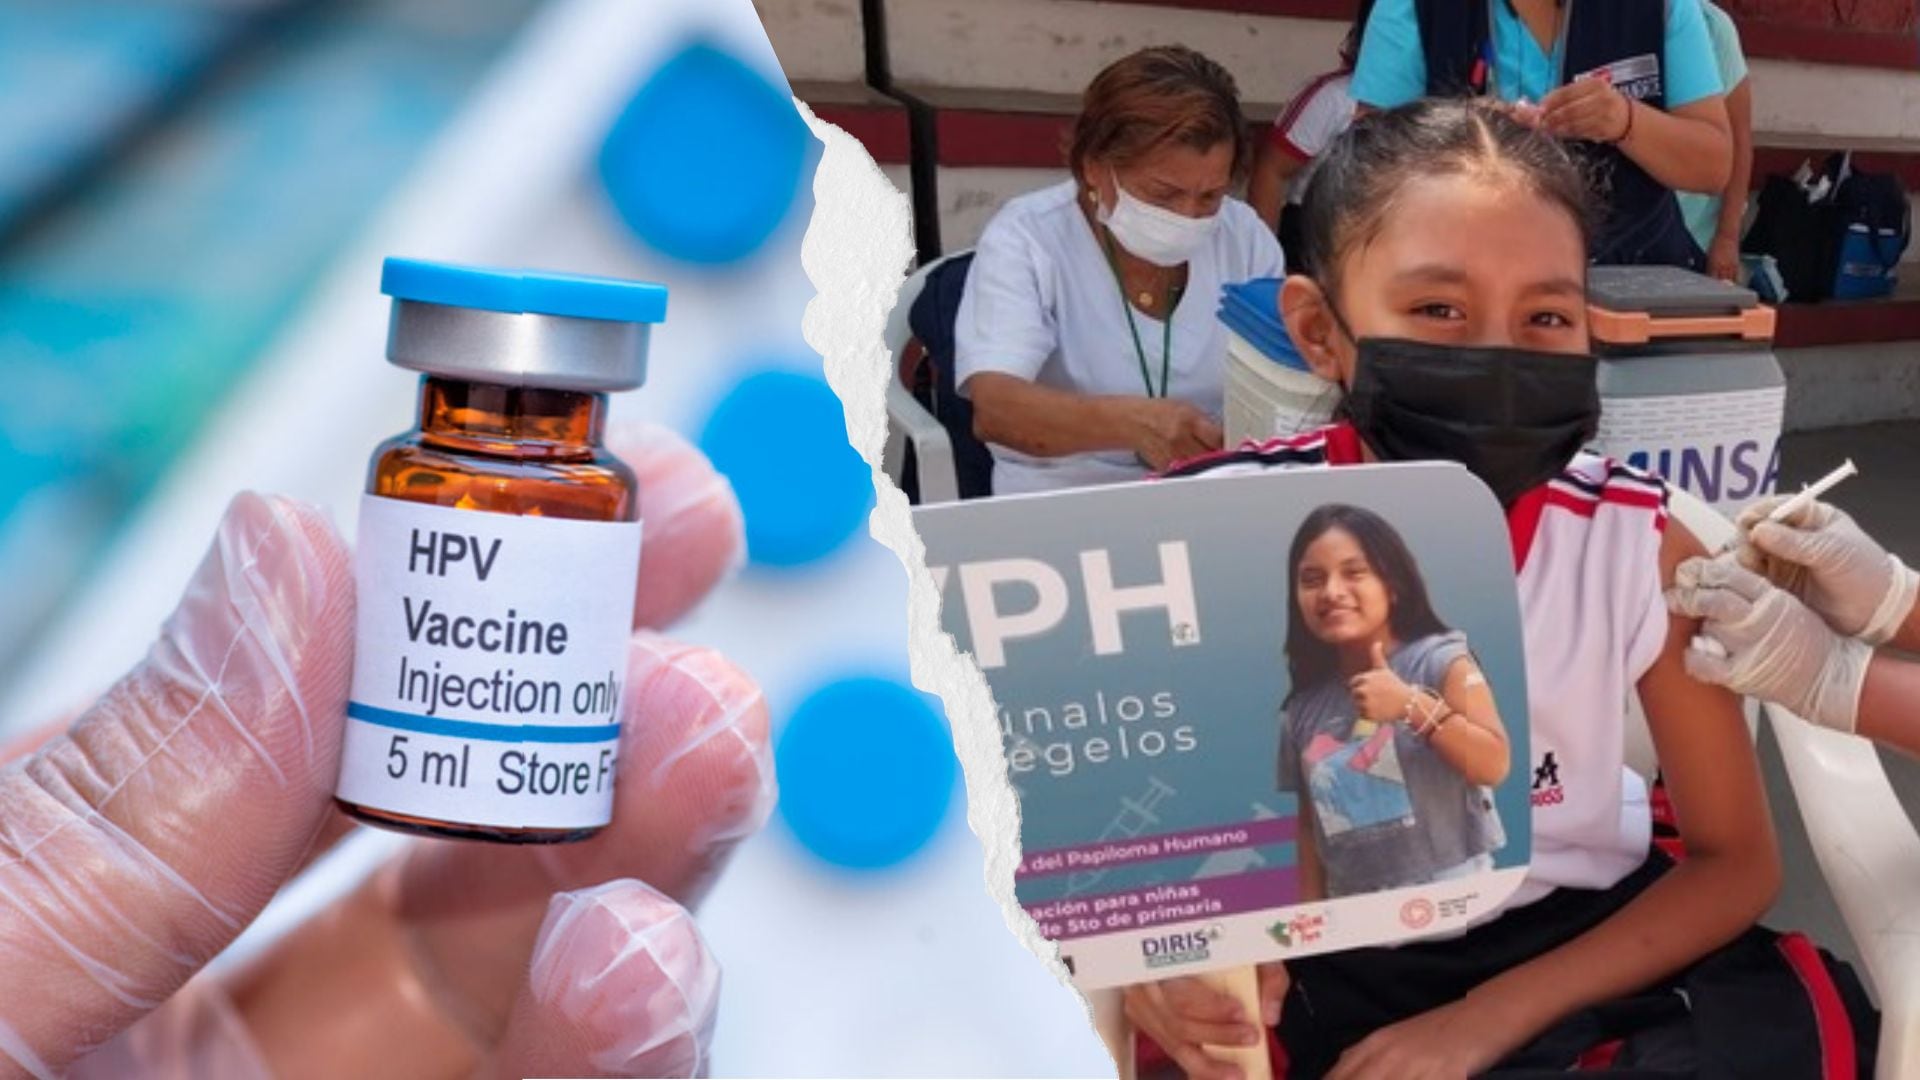

En Argentina, la disminución sostenida de la vacunación entre niños y adolescentes permitió que el Virus del Papiloma Humano (VPH) gane terreno y refuerce su posición como el agente infeccioso de transmisión sexual más frecuente a nivel global.

En el Día Mundial de concientización contra el VPH, las cifras oficiales muestran que, a lo largo de la última década, la cobertura de la vacuna contra el VPH cayó de forma progresiva: en 2024, la inmunización alcanzó apenas el 55,5% de las mujeres y el 50,9% de los varones, según datos de la Dirección de Control de Enfermedades Inmunoprevenibles, dependiente del Ministerio de Salud de la Nación.

La vacuna contra el VPH, incorporada al Calendario Nacional de Vacunación (CNV), fue un hito en la lucha contra el cáncer de cuello uterino y otras consecuencias graves del virus. La OMS impulsa la estrategia 90-70-90 para la eliminación de esta enfermedad, que propone vacunar al 90% de las niñas antes de los 15 años, garantizar que el 70% de las mujeres accedan a pruebas de detección a los 35 y 45 años, y asegurar que el 90% de las mujeres diagnosticadas con lesiones precancerosas reciban tratamiento.

El VPH representa la principal causa del cáncer de cuello uterino y está vinculado a una multiplicidad de patologías graves. La Organización Mundial de la Salud (OMS) estima que cuatro de cada cinco personas sexualmente activas lo contraerán en algún momento de su vida.